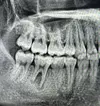

الدكتور آدم دمير طبيب أسنان

ألم الأسنان

تسوس الأسنان

نقص الأسنان

عدم انتظام الأسنان

أمراض الأسنان واللثة